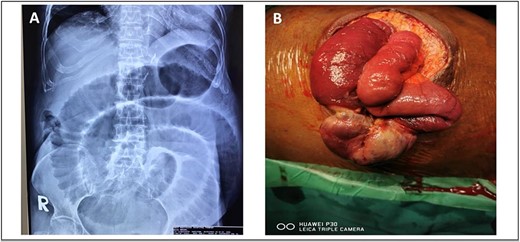

A 52-year-old Malay man, an active smoker, with underlying pulmonary hypertension secondary to atrial septal defect secundum with Eisenmenger syndrome and chronic lung disease. He had been experiencing symptoms of intestinal obstruction for a week. He had abdominal pain for 1 day, vomiting for 2 days, and unable to pass motion for the past 1 week. Patient was tachypnoeic with a respiratory rate of 35/min, a pulse rate of 116 bpm, and SPO2 of 90% under high-flow nasal cannula 50%/50 L. Abdominal radiograph showed dilated large bowel. Computed tomography abdomen and pelvis revealed short segment circumferential enhancing bowel wall thickening at rectosigmoid region causing intraluminal obstruction and presence of target sign at left lumbar region suggestive of jejunojejunal intussusception (Figs 2 and 3).

(A) Axial view and (B) coronal view of computed tomography showed presence of doughnut sign at left lumbar region suggestive of jejunojejunal intussusception (red arrow).